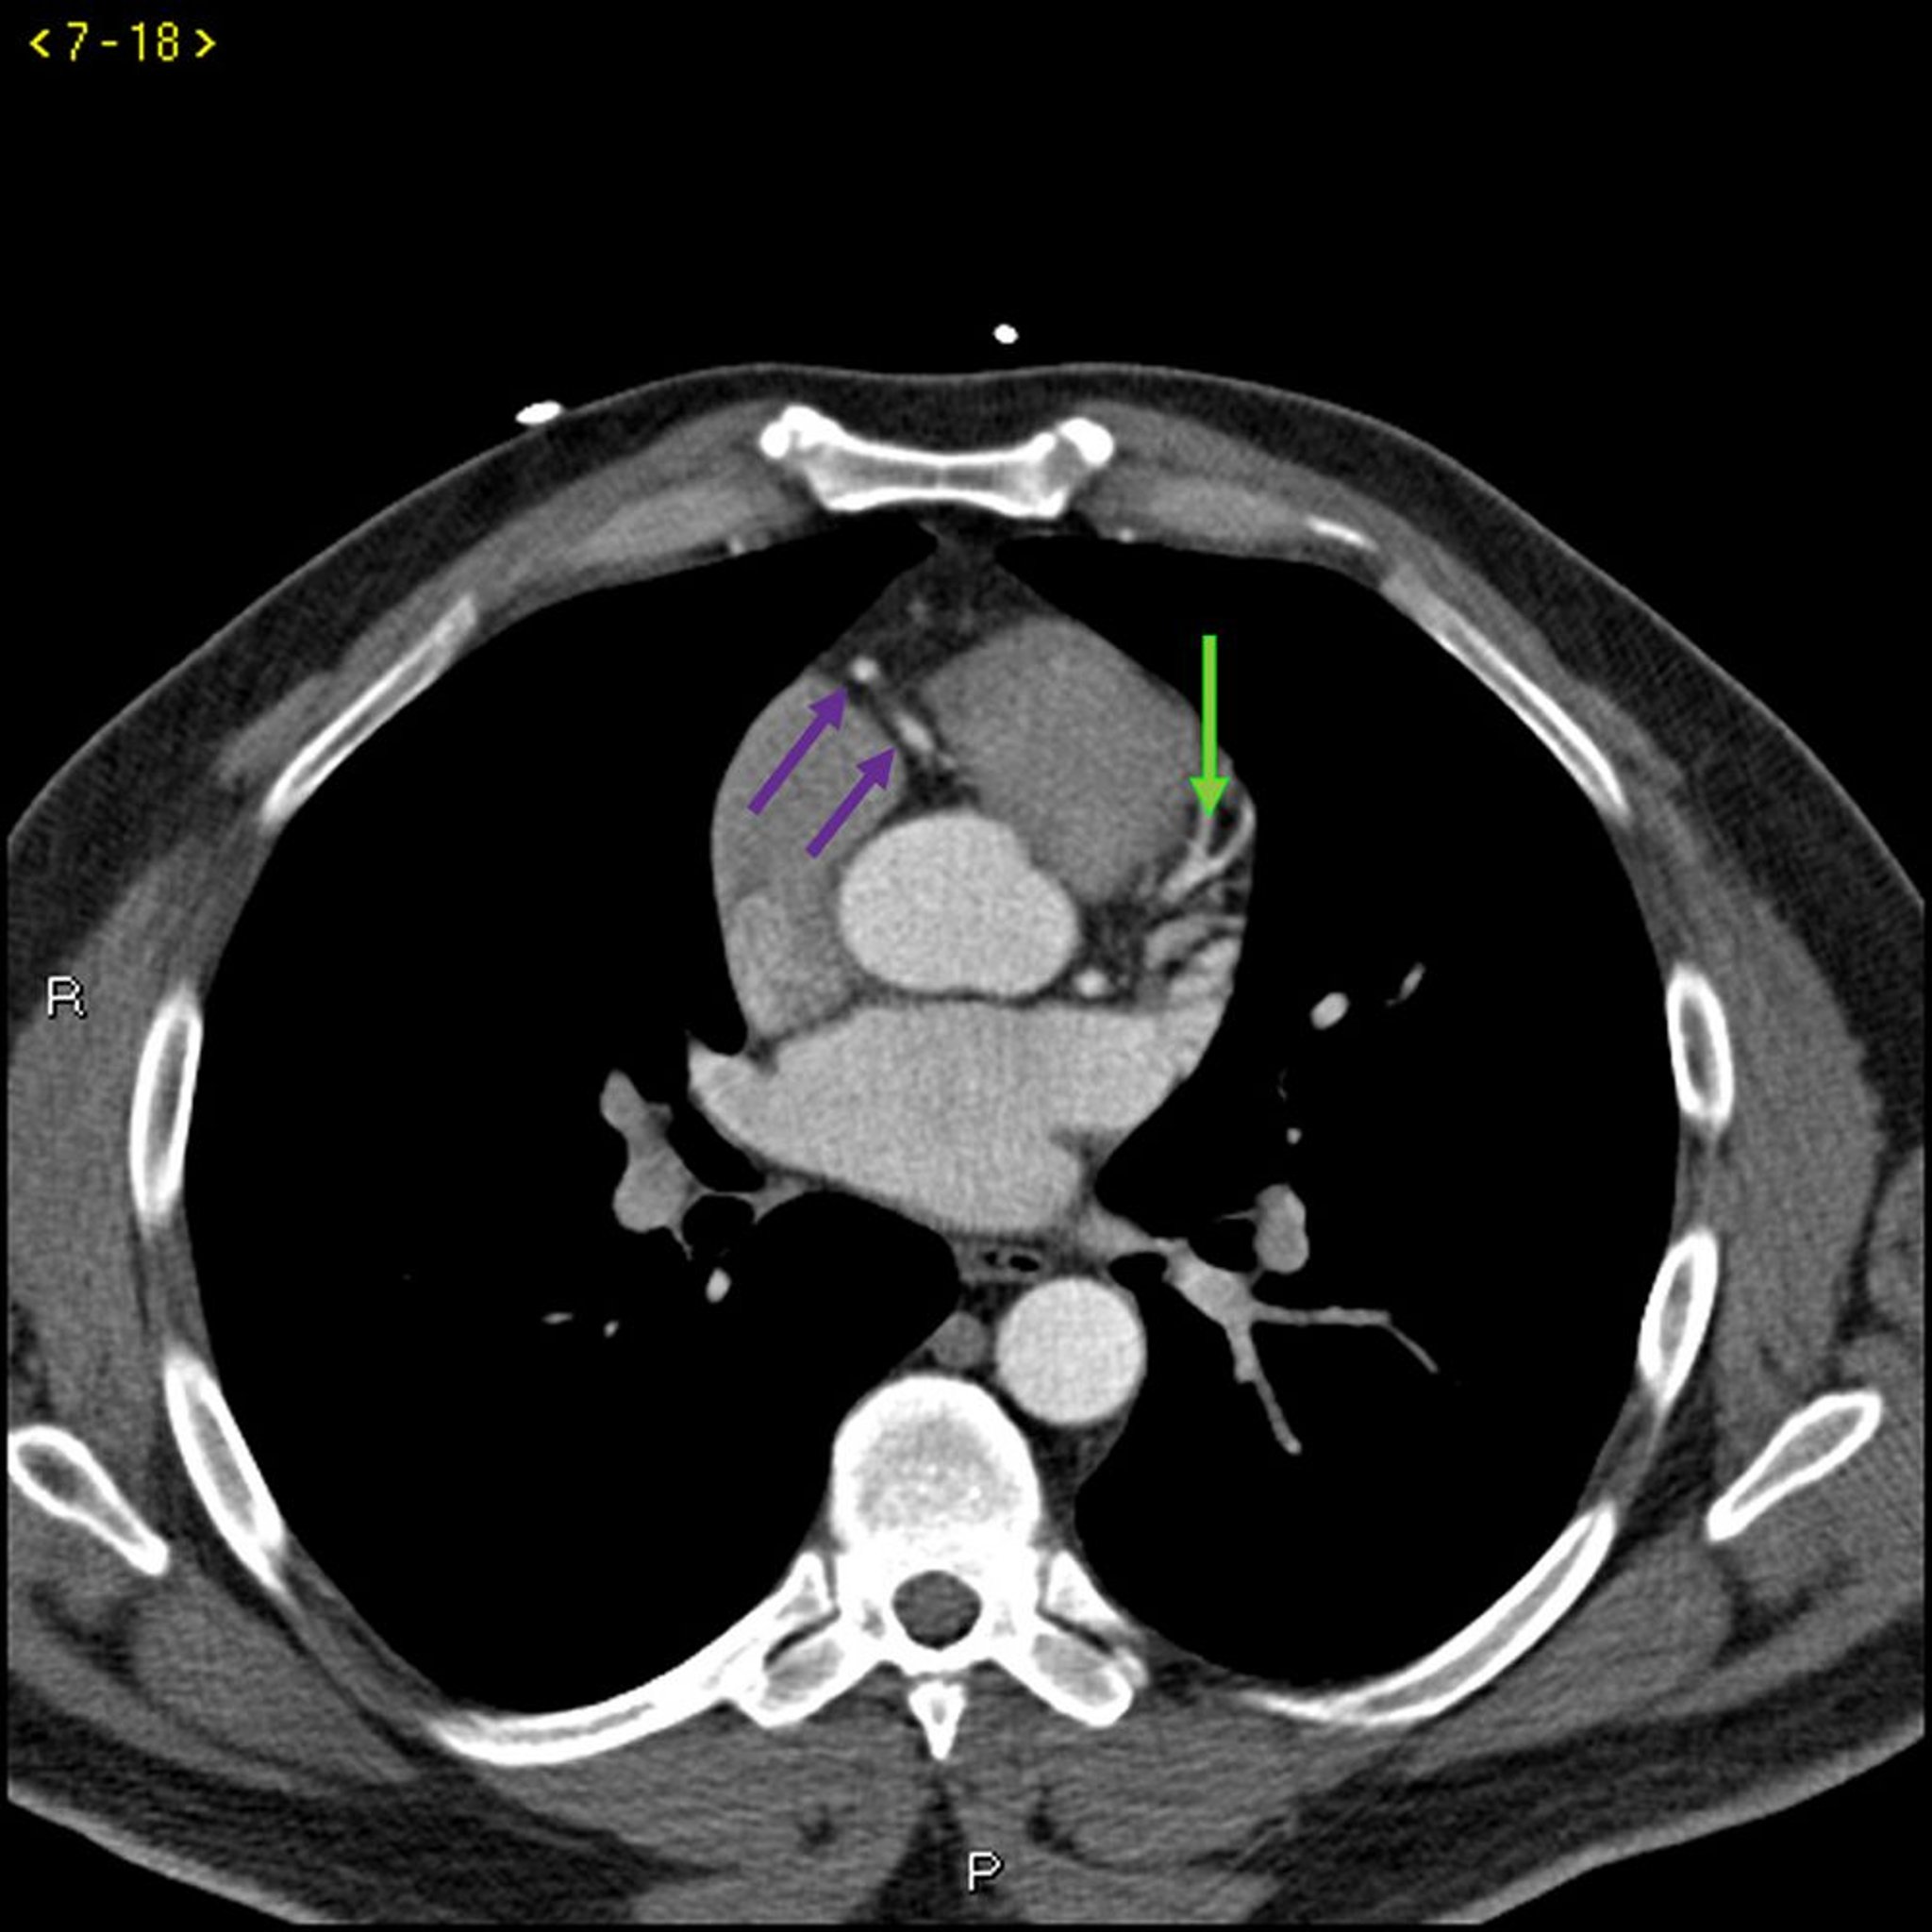

TC com contraste mostrando artérias coronárias normais – Diapositivo 3

Essa TC com contraste mostra artérias coronárias normais. A artéria esquerda principal é indicada pela seta vermelha. As artérias descendente anterior esquerda e circunflexa esquerda são indicadas pelas setas verde e azul, respectivamente, e a artéria coronária direita é indicada pela seta roxa.